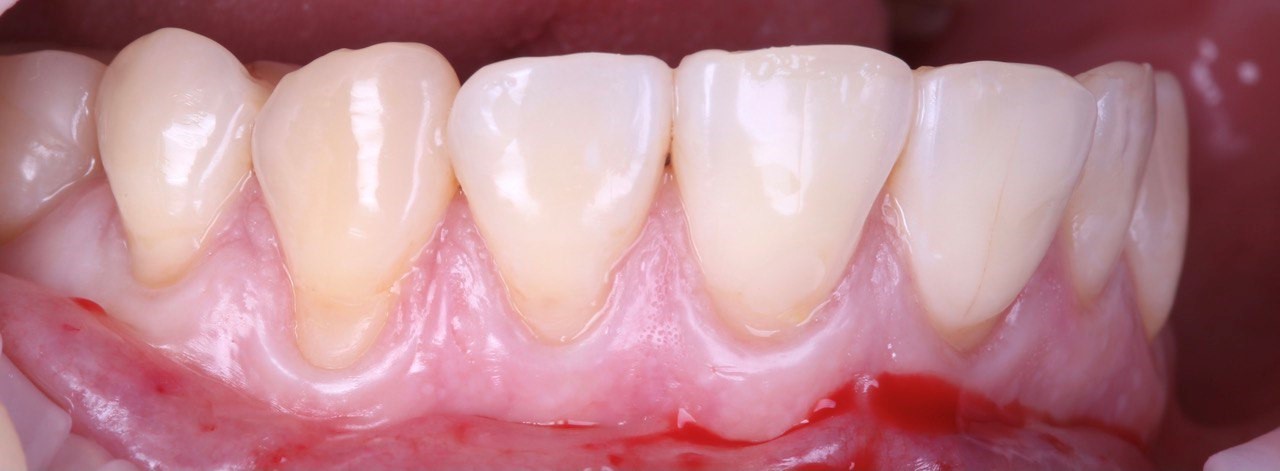

Сама операция проводится по следующей схеме:

- проводится предварительная санация ротовой полости, применяется местная анестезия;

- от альвеолярной кости частично отделяется участок «родной» десны, образуется карман, в который затем будет подсажен трансплантат;

До пластики